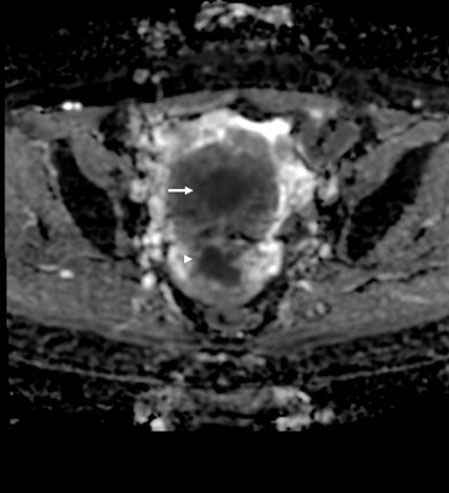

Figure 2: Magnetic resonance imaging (MRI) apparent diffusion coefficient (ADC) map sequence; axial section showing low ADC values in the cervical mass (white arrowhead) and uterine corpus mass (white arrow). The masses had similar low ADC values, but the cervical mass had a slightly lower ADC value compared with the uterine corpus mass.

Magnetic resonance imaging was performed to confirm the nature of the mass in the uterus. The lobulated and well-defined masses in the cervix and corpus of the uterus displayed similar relatively high signal intensity on the T2-weighted images (Figure 1). They also both showed a low apparent diffusion coefficient (ADC) value (Figure 2). Moreover, the masses appeared to be contiguous at the cervix on the T2-weighted images. This finding differed from what was observed using transvaginal ultrasonography.

Because CCS is a very rare tumor, few comprehensive imaging studies have been published. However, Li et al. [26] reported that three cases of CCS showed a cervical mass with cystic and solid components with heterogeneous enhancement. They presented a mixed or low signal intensity on the T1-weighted images and a mixed or high signal intensity on the T2-weighted images. In our case, the MRI initially suggested that the CCS and endometrial adenocarcinoma appeared to be the same lesion. Retrospectively, the CCS showed an apparently stronger and more heterogeneous enhancement on the contrast fat-suppressed T1-weighted images, as well as a relatively higher signal intensity on the T2-weighted images and lower ADC value compared with the endometrial adenocarcinoma. It is unclear why the CCS showed a higher signal intensity on the T2-weighted images and lower ADC value. However, the CCS showed heterogeneous enhancement potentially because it contained multiple different components.